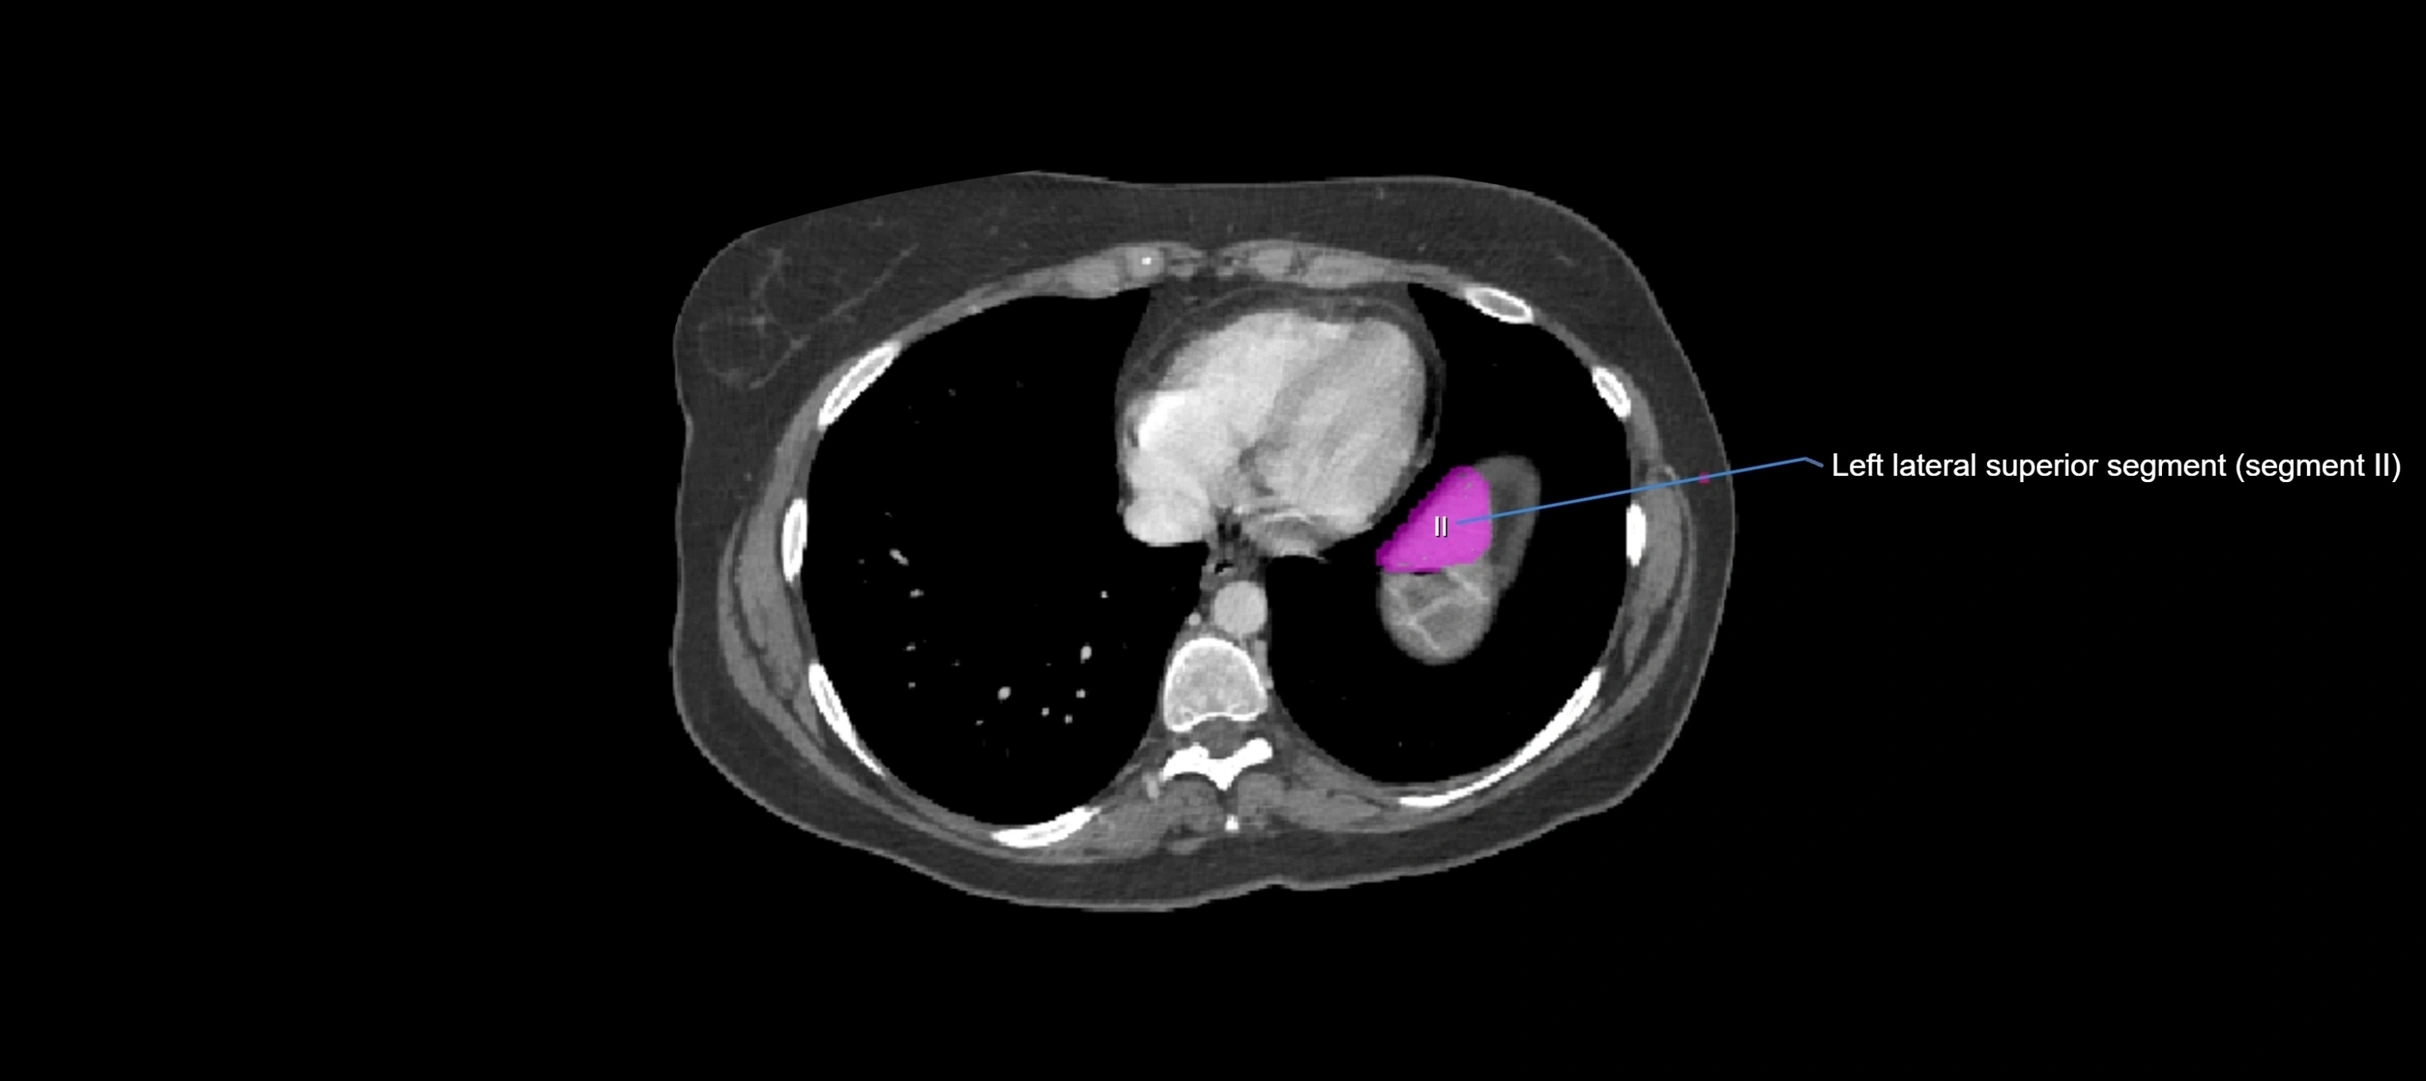

CT Image

image